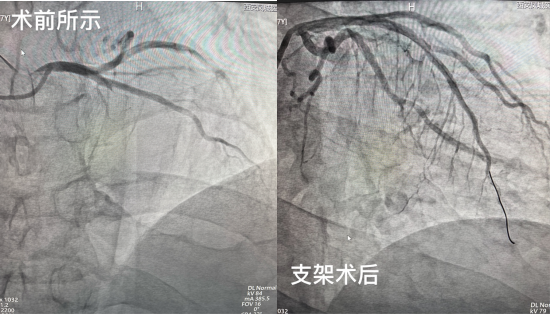

术中,心血管内科王东琦主任、薛虹主任的介入团队沉着应战,凭借丰富的临床经验与精准的操作技巧,快速完成血管造影。造影结果显示,患者冠状动脉前降支完全闭塞,这正是导致急性心梗的“罪魁祸首”。在与家属充分沟通并获得手术同意后,立即制定支架置入治疗方案,在 DSA 引导下,精准将—枚支架成功置入闭塞血管,瞬间恢复了心肌的血液供应。整个手术过程紧张有序、精准高效,于 23 时 10 分顺利结束,患者生命体征平稳, 术后安返病房接受进一步监护治疗。